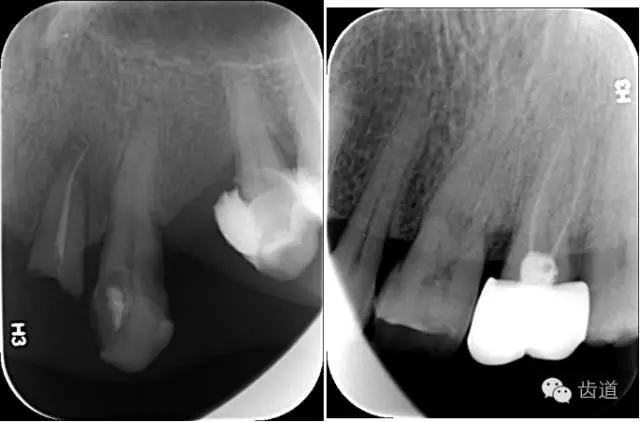

6、輔助檢查

X線:根尖片、曲面斷層片(牙槽嵴頂,水平垂直吸收,程度)